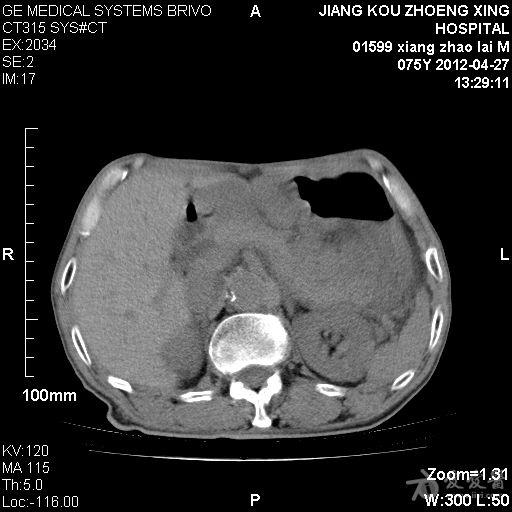

一位高龄患者肝脏点位伴胆囊结石病例讨论

图片尺寸912x876